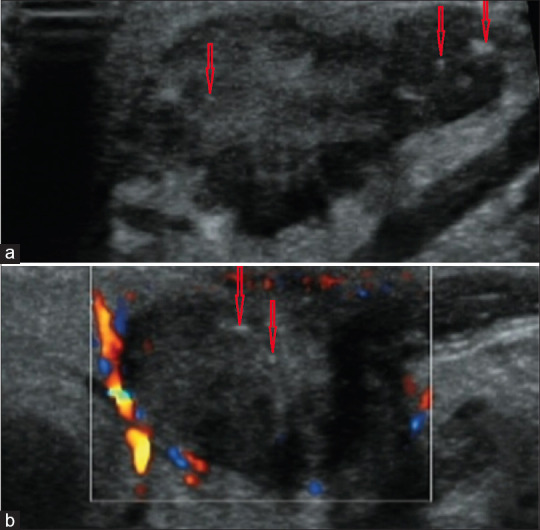

Knowledge of the color Doppler ultrasound (US) characteristics of parotid malignant mucoepidermoid carcinoma and benign basal cell adenoma remains limited. To enhance understanding of these two diseases, we retrospectively analyzed 9 cases of surgically and histopathologically confirmed mucoepidermoid carcinomas and 18 cases of basal cell adenomas. The results revealed that mucoepidermoid carcinomas exhibited irregular and deeply lobulated shapes in 55.5% of cases, ambiguous margins in 88.8%, and punctuate calcifications in 66.7%. In contrast, basal cell adenomas demonstrated regular and shallowly lobulated shapes in 72.2% of cases, clear margins in 100%, and calcifications in only 5.6%. Significant differences were observed in these characteristics between the two tumor types. Therefore, we conclude that the color Doppler US features closely associated with mucoepidermoid carcinoma include deeply lobulated or irregular shapes, ambiguous margins, and punctate calcifications. Recognizing these characteristics can facilitate the differential diagnosis of the two kinds of tumors.

Abstract Image